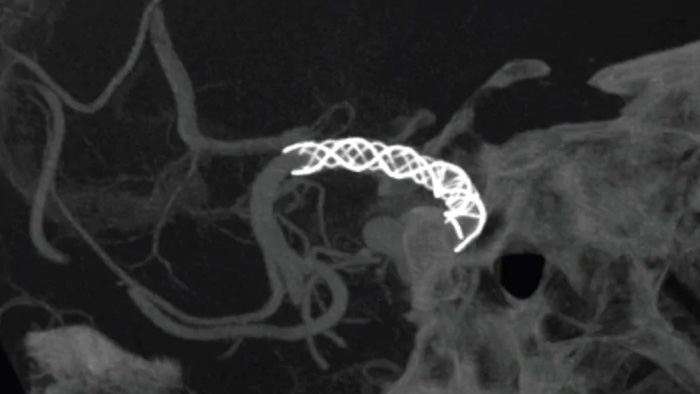

Améliorez la visualisation des stents endovasculaires, des flow diverters et d’autres dispositifs, ainsi que la morphologie des vaisseaux jusqu’à la veine perforante avec SmartCT Vaso. Cette technique d’acquisition est basée sur une acquisition Cone Beam CT et une injection de produit de contraste intra-artérielle. Elle est de plus en plus utilisée pour le suivi des anévrismes traités avec des stents de flow diverter afin de vérifier le positionnement du dispositif.